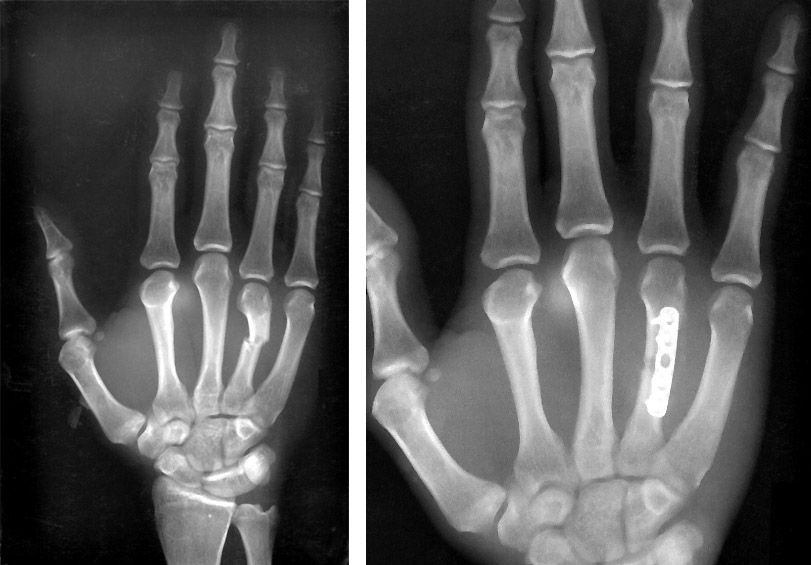

Metacarpal fracture and internal fixation

(Left) X-ray shows a metacarpal fracture of the ring finger. (Right) Here, the fracture has been repaired with a plate and screws.

Reproduced from Kozin SH, Thoder JJ, Lieberman G: Operative Treatment of Metacarpal and Phalangeal Shaft Fractures. J Am Acad Orthop Surg 2000;8:111-121.